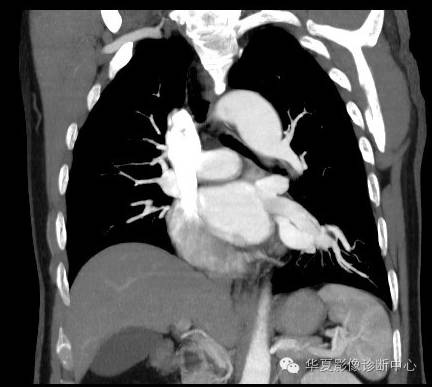

| 影像表现及分析: | 影像表现:定位左下叶;左下叶体积缩小,整体密度增高,支气管分布正常,其内见血管增多,但是走形正常,未见杂乱、迂曲的血管影;血管连向肺门下方软组织密度结节灶,结节与主动脉分界不清,增强后,见降主动脉发出异常粗大血管供血整个左下叶,左下肺动脉细小。 |

| 确诊依据: | CTA明确左下叶供血动脉为降主动脉发出 |

异常体动脉供应正常下肺基底段完整含义为起源于降主动脉的异常动脉供应下肺基底段,而基底段支气管树和肺实质正常,同时基底段肺动脉缺如或狭窄【大部分缺如(完全型),部分狭窄(不完全型)】;95%以上累及左下肺,因此也称为异常体动脉供应正常左下肺基底段。 病因尚未明确,可能是胚胎发育时期供应肺芽的背主动脉原始小分支退化不全,与肺实质形成异常连接,并影响肺动脉与肺血管床连接而导致此部位肺动脉发育不良,而支气管、肺组织的发育未受影响。本病的病理生理基础为左向左的分流,体动脉供应的肺组织充血,体循环的高压可增加肺血管床的压力和左心负荷,同时也增加肺循环量和压力而增加右心负荷,导致各种临床症群。本病可无临床症状,部分患者可有咯血、呼吸道感染、呼吸困难、充血性心力衰竭。 影像表现:左肺下叶体积缩小,整体密度稍增高,支气管树走形、分布正常,血管增多、稍增粗;增强后显示左下肺动脉幼小,甚至不发育;下叶由主动脉发出的粗大血管供血。 |